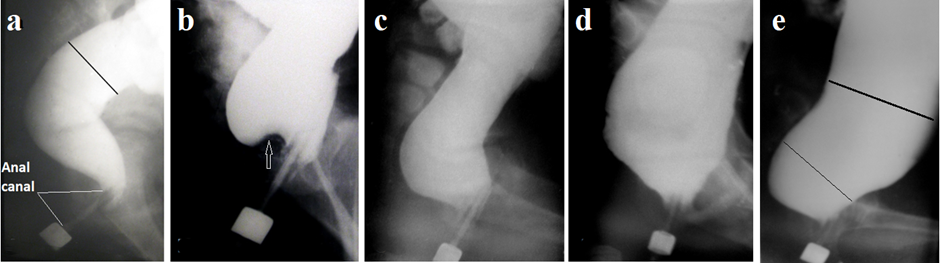

Figure 2 presents frontal radiographs of the colon during various stages of functional megacolon:

Figure 2. Frontal radiographs during the barium enema.

a) Normal anatomy: the rectum is not visible as its branches overlap in two projections. The sigmoid colon (s) is of normal caliber and located in the pelvis.

b) Grade 2 megacolon: the sigmoid colon is elongated and dilated.

c) Grade 3 megacolon: marked sigmoid and colonic dilation.

d) Advanced FM with colitis: asymmetrical haustration and poorly defined, "fluffy" colonic contours indicate inflammation. The dilated, elongated sigmoid colon reflects a history of severe constipation. Here, inflammation induced by prolonged fecal stasis narrowed the colonic lumen, leading to easier passage of stool and relief of constipation symptoms [18,19].